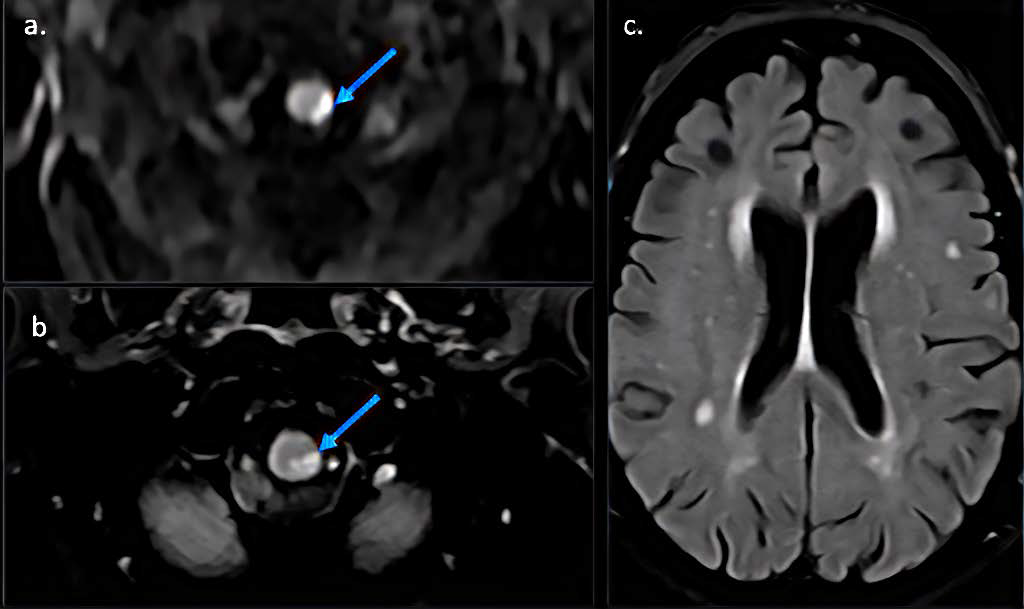

A Case of Listeria Rhomboencephalitis with Misleading Imaging Presentation and Laboratory Findings

Adrien De Minteguiaga, Anna Paola Bocchio, MD, Valeria Onofrj, MD

1-6